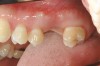

Figure 2  Removable prostheses can provide proper support and enhance overall facial esthetics for the patient.

Figure 2

Figure 3  Removable prostheses can provide proper support and enhance overall facial esthetics for the patient.

Figure 3